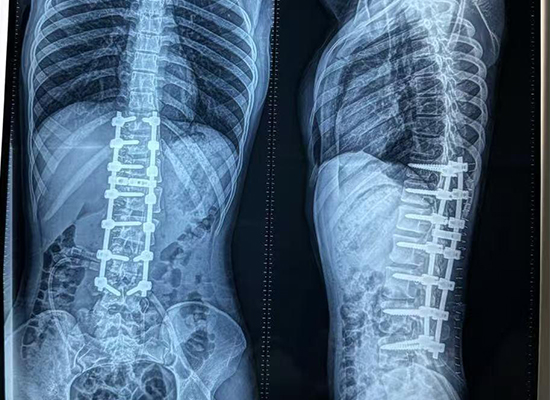

Послеоперационная визуализация продемонстрировала:

Значительное улучшение выравнивания позвоночника.

Уменьшенная кривизна и выступание ребер.

Сбалансированные плечи и туловище

Клинически Раиса показала:

Стабильный неврологический статус

Удовлетворительный контроль боли

Постепенное возвращение к стоянию и ходьбе с поддержкой.

Улучшение осанки и косметический внешний вид

Под тщательным наблюдением пациент продолжал плавно выздоравливать, а ранние результаты предполагали благоприятный долгосрочный прогноз для баланса позвоночника и качества жизни.